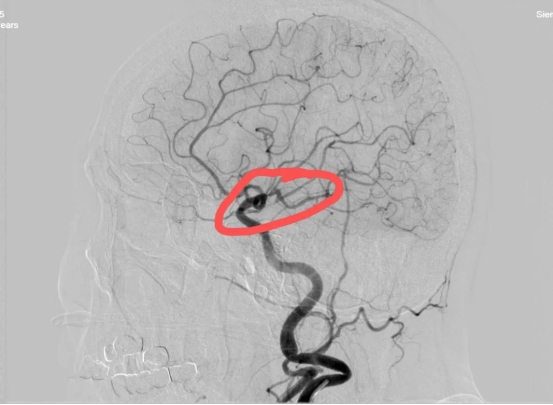

头颅CT和血管评估确诊为:急性右侧大脑中动脉栓塞。

“血管检查时,病变位置相当隐蔽,被其他血管挡住了。”李威描述,“我们换了好几个角度,才找到藏在末梢的血栓——它没有完全堵死,一丝血流还在渗过去,但主干血管确实卡住了。”

手术台上,神经内科介入团队凭借丰富经验,在DSA引导下,将取栓支架精准送达堵塞的右侧大脑中动脉,一次性取栓成功。

术前影像(左)和术后影像(右)

当造影显示血流恢复通畅时,手术室里的医护人员都松了口气,老人的大脑功能有了恢复的可能。